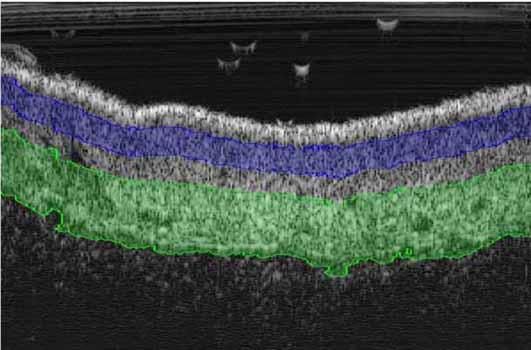

Software de post-procesamiento de imágenes

Atys, en colaboración con Creatis (laboratorio de investigación en imagen médica: www.creatis.insa-lyon.fr ) a través de Labcom AtysCrea, ha desarrollado un software de post-procesamiento poderosa imagen grabada por el DERMCUP para la segmentación estructuras (tumores, …) presentes en la dermis.